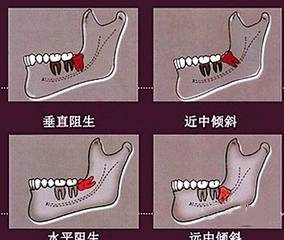

如果是反复疼痛的,出现阻生情况比如前倾、后倾、水平、倒置等现象的,这样的智齿最好还是拔掉,不好拔也得拔,因为它是没法长正的。而且,可能今年还只是智齿发下炎,过几年,它前面的邻牙很有可能被侵及,再拔牙就得拔一送一啦!